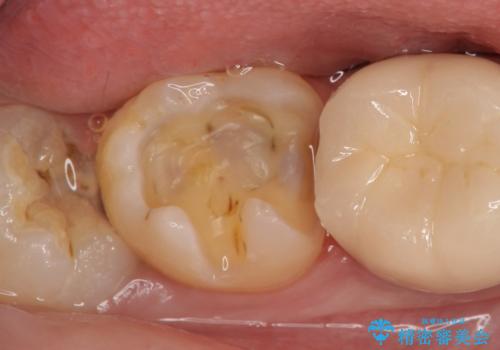

- 右下7の銀歯を白くしたいといらっしゃった方の症例です。

銀歯及び虫歯を除去後、セラミックインレーで修復を行いました。